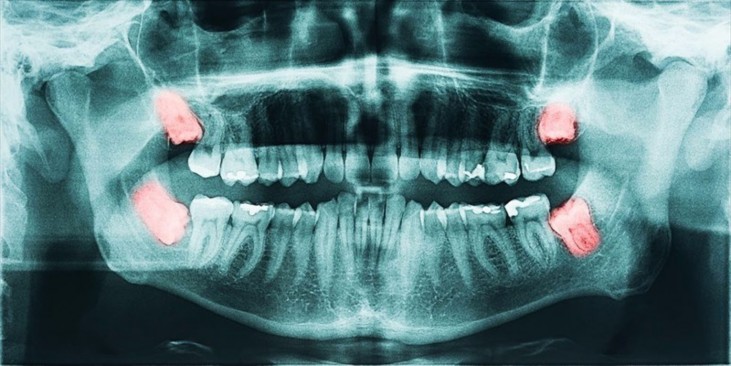

A wisdom tooth may get stuck or develop at an angle if there is not enough space to come through usually, we call this an impacted wisdom tooth.

If a wisdom tooth doesn’t come in properly or there isn’t enough room in your mouth, it can cause complications.

Impacted wisdom teeth can cause infection, pain, inflammation and other issues.

Dentists may recommend the removal of wisdom teeth as a precaution because they can cause long-term problems, like: